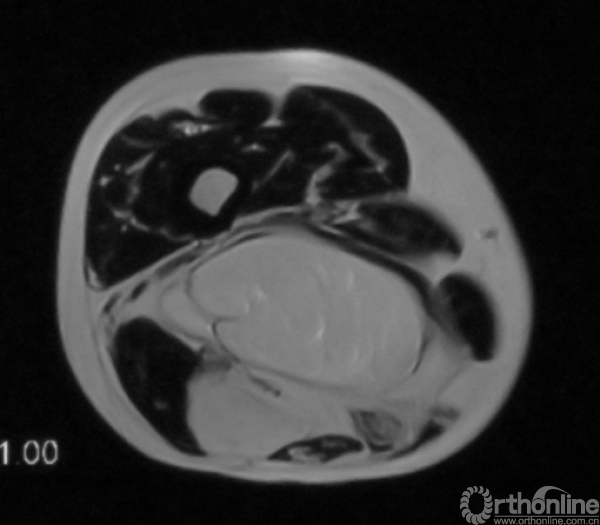

患者女,53岁,右大腿上段复发性高分化脂肪肉瘤。

术前磁共振提示肿瘤包绕坐骨神经,周围肌肉组织行R0切除,坐骨神经R2切除边界后行三明治隔离手术,术后随访28月未见复发。

术前磁共振影像